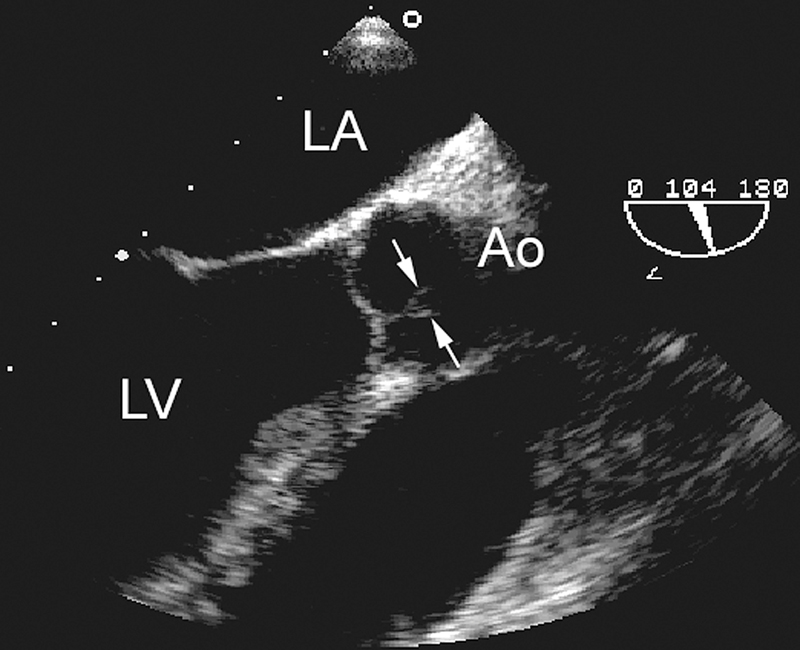

فحوصات تشخيصية لبعض امراض القلب والشرايين التاجية